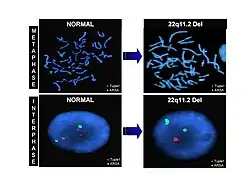

Fluorescence in situ hybridization (FISH), is an example of a genetic labeling technique that utilizes probes that are specific for chromosomal sites along the length of a chromosome, also known as chromosome painting. Multiple fluorescent dyes that each have a distinct excitation and emission wavelength are bound to a probe which is then hybridized to chromosomes. A fluorescence microscope can detect the dyes present and send it to a computer that can reveal the karyotype of a cell. This technique allows abnormalities such as deletions and duplications to be revealed.[24]